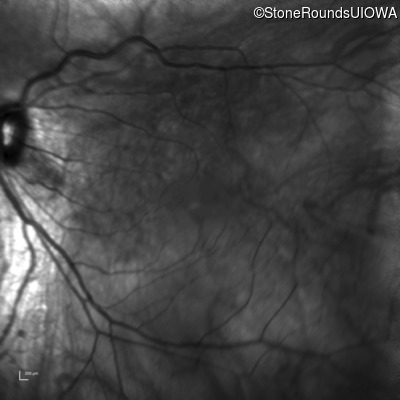

Infrared Fundus Photograph - Right - 20/25 -3

Exemplar